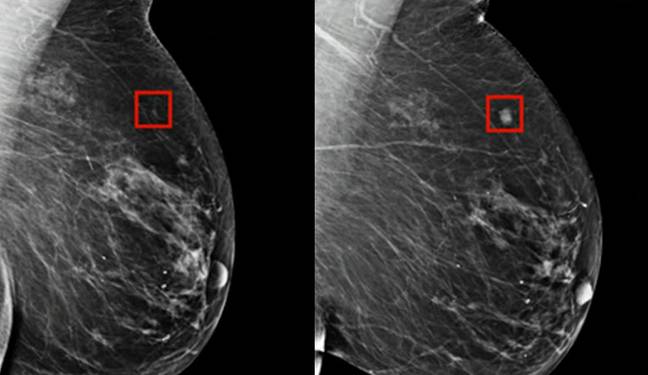

An AI program was successfully able to detect breast cancer in a woman four years before it developed.

“This technology can look at mammograms and identify areas that a human radiologist may want to look at more carefully.

“What this work does is it identifies risk. It can tell a woman ‘you’re at high risk of developing breast cancer’ before you develop breast cancer.”

They also report that the AI was tested with some of the most challenging cancer cases where the early signs of breast cancer had not been spotted by radiologists, with the AI successfully managing to identify the cancer.